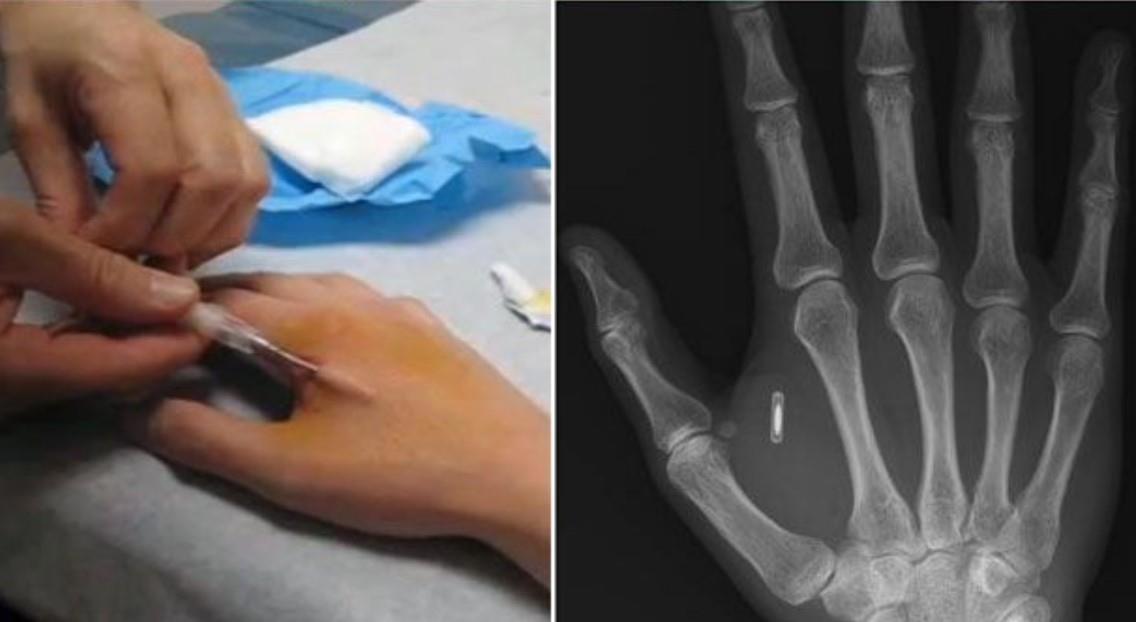

А плохо слышащий дядя Вася, в кохлеарным имплантом, или бородатый хипстер Вениамин, вжививший под кожу RFID капсулу, ради дешевых понтов, (открывания дверей офиса без пластиковой карты и прочей фигни), - даже рядом не машинные гибриды и уж тем более не киборги.

Итого: Старый стационарный телефон, с автоответчиком, это не смартфон. А человек с капсулой под кожей, размером с рисовое зерно, – не киборг.